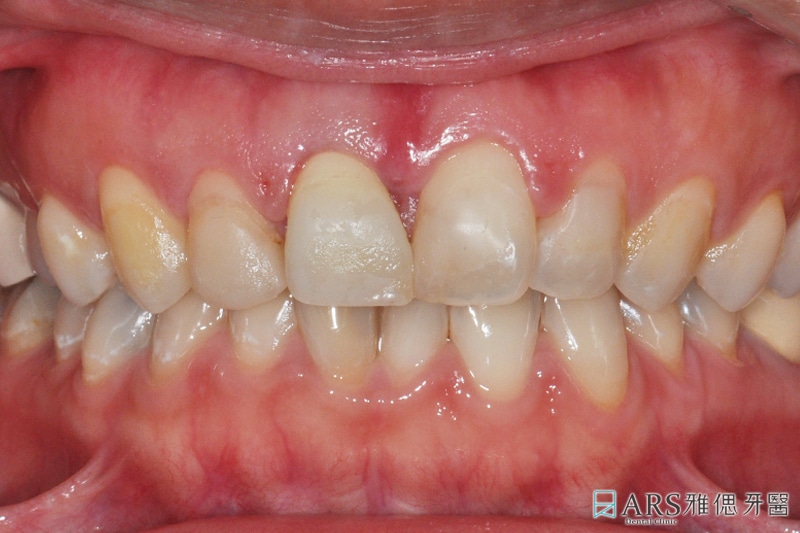

就診時 因為牙齦不整齊 笑的時候會有露牙齦的問題

且前牙牙套顏色及型態不好,牙齒的走向也不夠理想

建議病人進行牙齦整形及臨時牙套設計

調整牙齦曲線 與微笑曲線